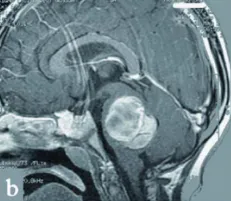

图1,a-c术前:显示患儿巨大的桥脑海绵状血管瘤。

入院时,妮娜存在躯干共济失调。她几乎无法维持坐姿,且不能站立。伴有轻度面瘫和重度右侧偏瘫,同时存在反射亢进和巴宾斯基征阳性(提示发生了中枢神经系统上运动神经元性损害)。再次复查MRI显示,左侧桥脑有一个最大尺寸为4×3.5×3cm的巨大海绵状血管瘤(图1,a-c)。

术后,患儿的神经症状持续改善。手术10天后进行的MRI检查证实海绵状血管瘤已被完全切除,并显示先前严重增大的脑干已得到减压(图1d)。妮娜出院后接受进一步的神经功能康复治疗。

d术后:显示海绵状血管瘤已完全切除,第四脑室大小恢复,脑干压迫解除。